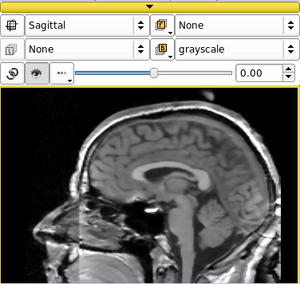

| qMRMLSliceWidget |

|

a 2D vtk render window with a controller |